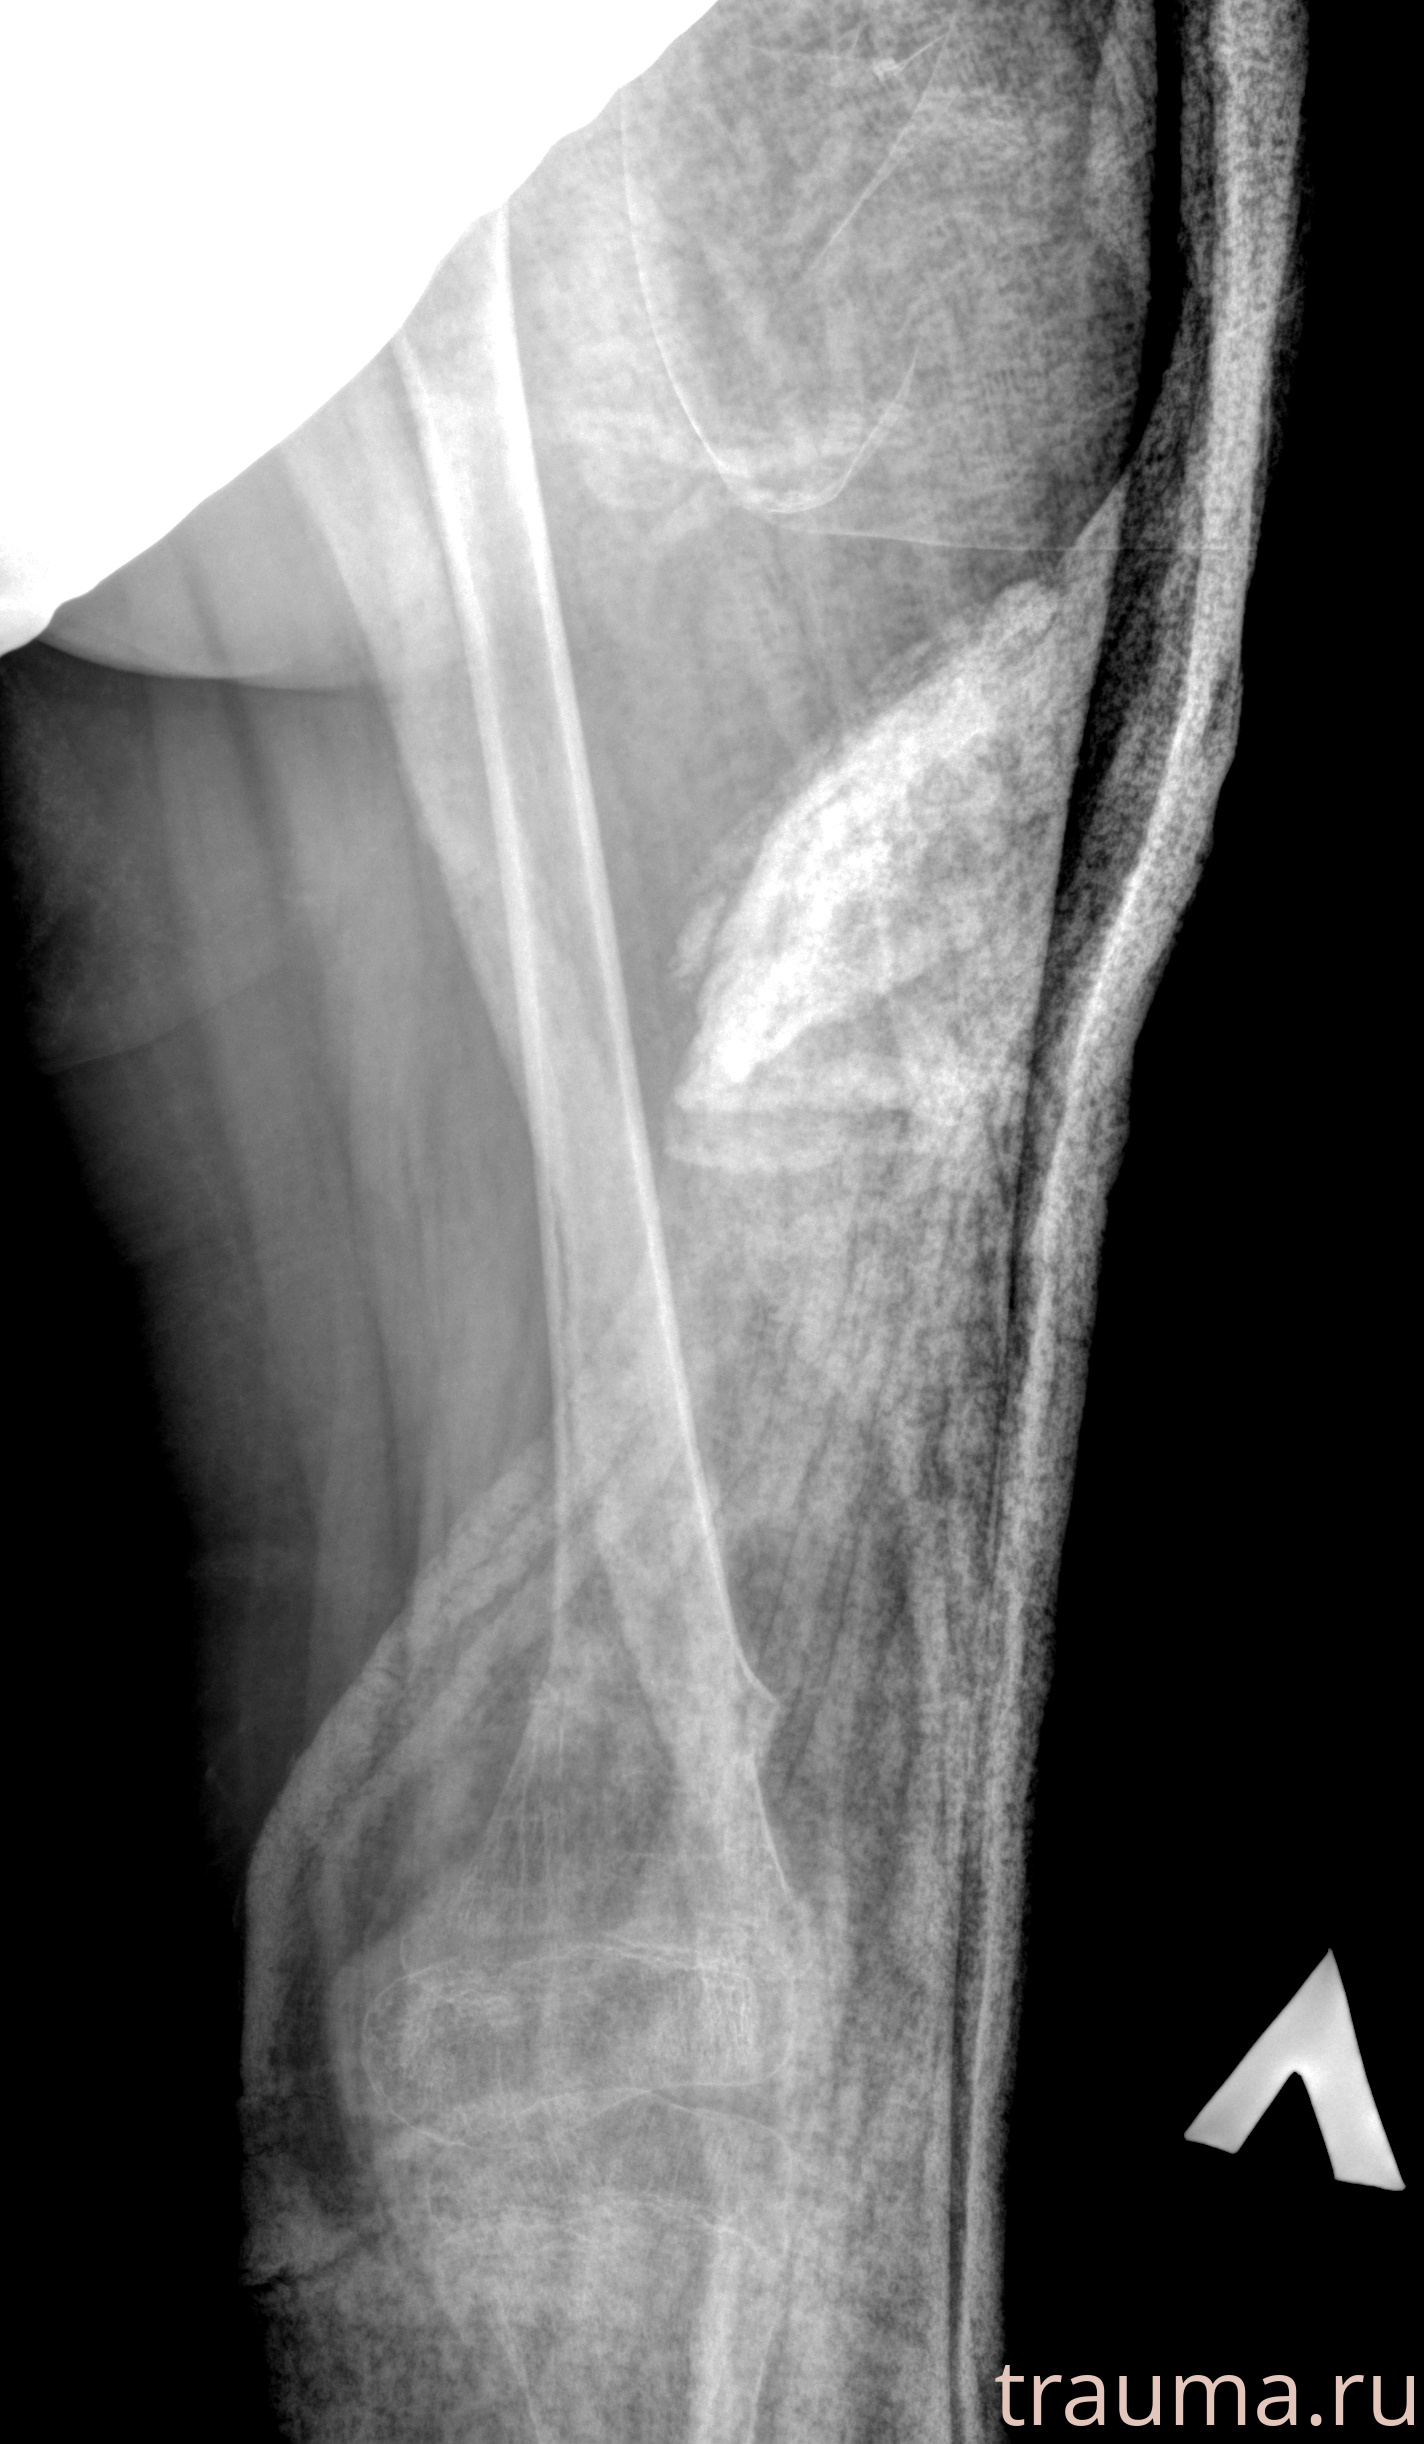

Рентгенограммы

Рентген на дому: по вашему адресу приезжает врач-рентгенолог, травматолог-ортопед с мобильным рентгеновским аппаратом, проводит диагностику травмы или заболевания, делает необходимые рентгенограммы, дает рекомендации по дальнейшему лечению. Получить качественные снимки в домашних условиях возможно благодаря уникальной методике, разработанной МосРентген Центром для института  Склифосовского